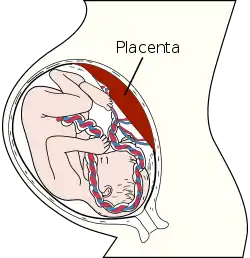

Francis John Mott (1901–1980) was a disciple of Fodor and the first author who concentrated on the placenta as the first object of the fetus.[34] He wrote, that the fetus fears his placenta as a "blood sucker" or experience it as a "feeder" or "life-giver".[35] His work an prenatal aspects is connected with his speculative assumptions on a quasi-religious design of the universe.

The US-American social scientist Lloyd deMause (born 1931) compiled in his essay from 1981 the psychoanalytic approaches to prenatal mental life as well as the physiological findings of the human ontogenesis concerning fetal development. He took several assumptions from the works of Grof and Mott, but left away their metaphysical implications completely. In his own approach he assumes, that the placenta becomes the first object of the fetus, namely in two split versions: a positive and a negative one, he called the "nurturing" and the "poisonous placenta".[36] DeMause presumed that in every gestation – especially at the end of this period – there are problems of supply with oxygen for the fetus. Because of physiological conditions the placenta would not be able anymore to supply the growing fetus with enough oxygen. This would give rise to states of pain and deprivation. Pre- and perinatal experiences lead to a mental script, a kind of pattern, to which later experiences would be connected with and internalized. He calls the experience of successive good and painful states the "fetal drama", long precursing the well known "oedipal drama" sensu Freud. Besides these theories about prenatal psychology deMause also developed approaches in the field of psychohistory – a system of cultural psychological assumptions, which explain historical processes and phenomenons by using psychological theories. Especially aspects of childhood history and prenatal psychology play an important role.